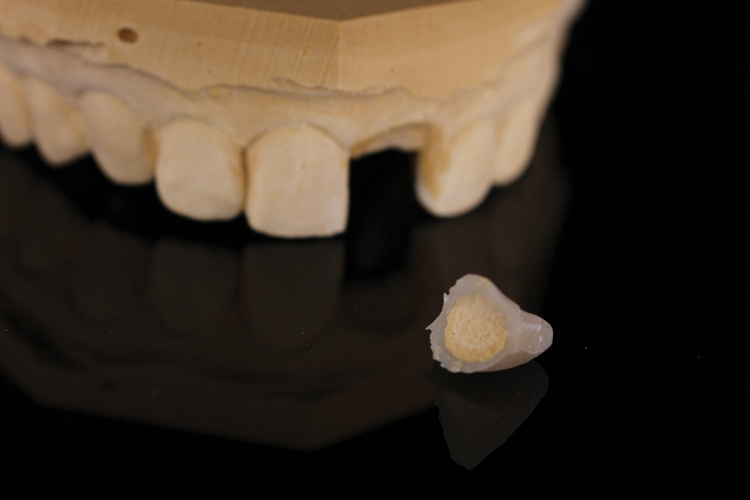

(45.) A patient presented for the replacement of the maxillary left central incisor with a bonded pontic made from the natural tooth, which was removed.

Figure 45

(48.) The natural tooth pontic was modified into a shell that resembled a three-quarter crown restoration, and then it was etched and bonded.

Figure 48

(49.) The natural tooth pontic was modified into a shell that resembled a three-quarter crown restoration, and then it was etched and bonded.